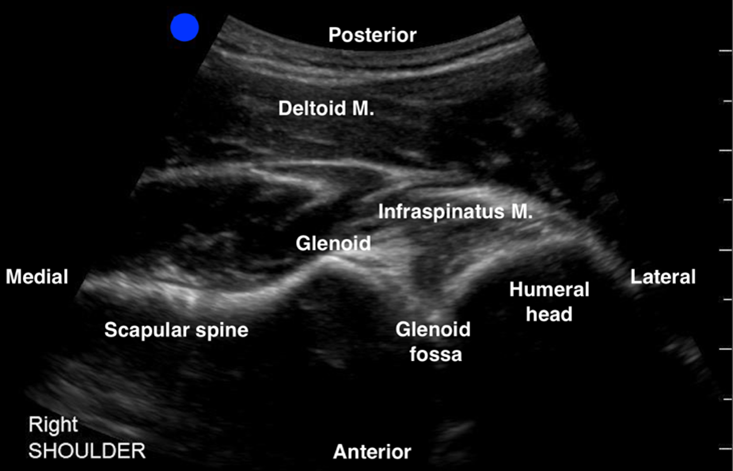

- The scapular spine can be identified as a hyperechoic line with a posterior shadow. Note that the deltoid and the infraspinatus muscles can be seen above the scapular spine (See Figure 1).

- Continue sliding the probe laterally along the scapular spine towards the glenohumeral joint (GHJ), until visualizing the glenoid fossa which is closely followed by the humeral head (See Figure 1). Positioning the glenoid fossa and the GHJ in the center of the screen while adjusting the depth, will result in a better image quality. Asking the patient to externally and internally rotate the affected shoulder will aid in identifying the humeral head (See Figure 2).

Figure 1: Normal right shoulder